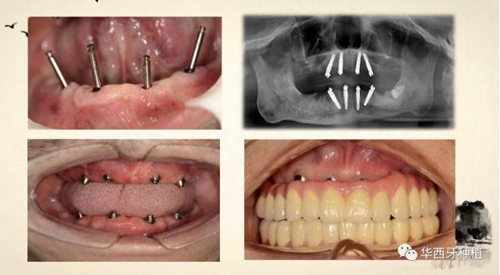

吳教授特別針對手術難度更大的all-on-four修復做了詳細的關于概念、設計、操作、修復的描述,首先是針對難度最大的手術環(huán)節(jié),就解剖、微創(chuàng)操作分別加以闡述。將他自己在臨床工作中的寶貴經(jīng)驗分享給了大家。

對于傳統(tǒng)的all-on-four術式,吳教授加入了微創(chuàng)的指導思想,設計時同樣加入數(shù)字化三維重建與修復一體化設計,增加了手術的可控性,同時極大減輕了患者的創(chuàng)傷程度,縮短了修復周期。

但是,他同時提到了此種修復方式操作難度要求很高,僅適合有經(jīng)驗的種植醫(yī)生操作。